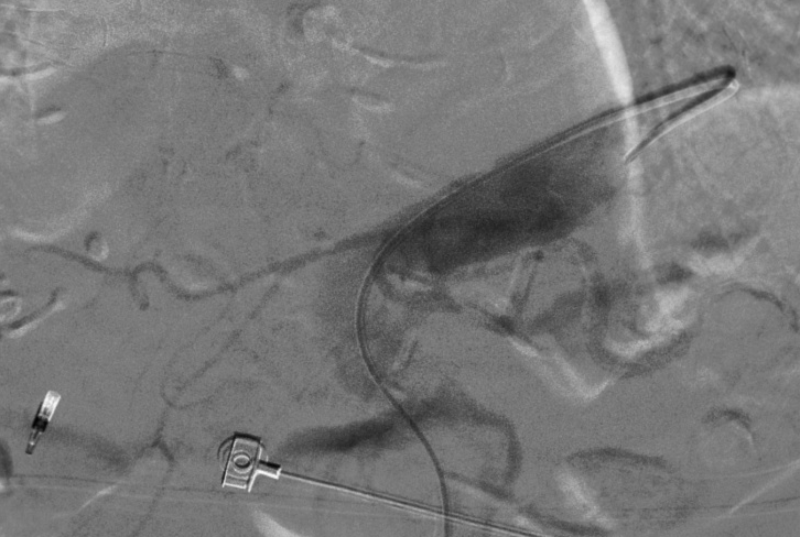

术中造影显示胸腹主动脉呈现2个S型弯曲,RH造影导管插入腹腔干非常困难,无法找到腹腔干。

更换造影导管及反复尝试后,导管进入腹腔干动脉。